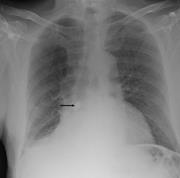

Delayed presentation of an aspirated capsule endoscope

Rohit A. Singh and others

Journal of Surgical Case Reports, Volume 2013, Issue 9, September 2013, rjt082, https://doi.org/10.1093/jscr/rjt082